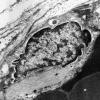

Giant Axonal Neuropathy (GAN) (6)